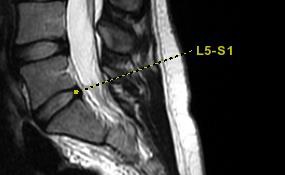

Figure 1. Example of an image with linked annotation